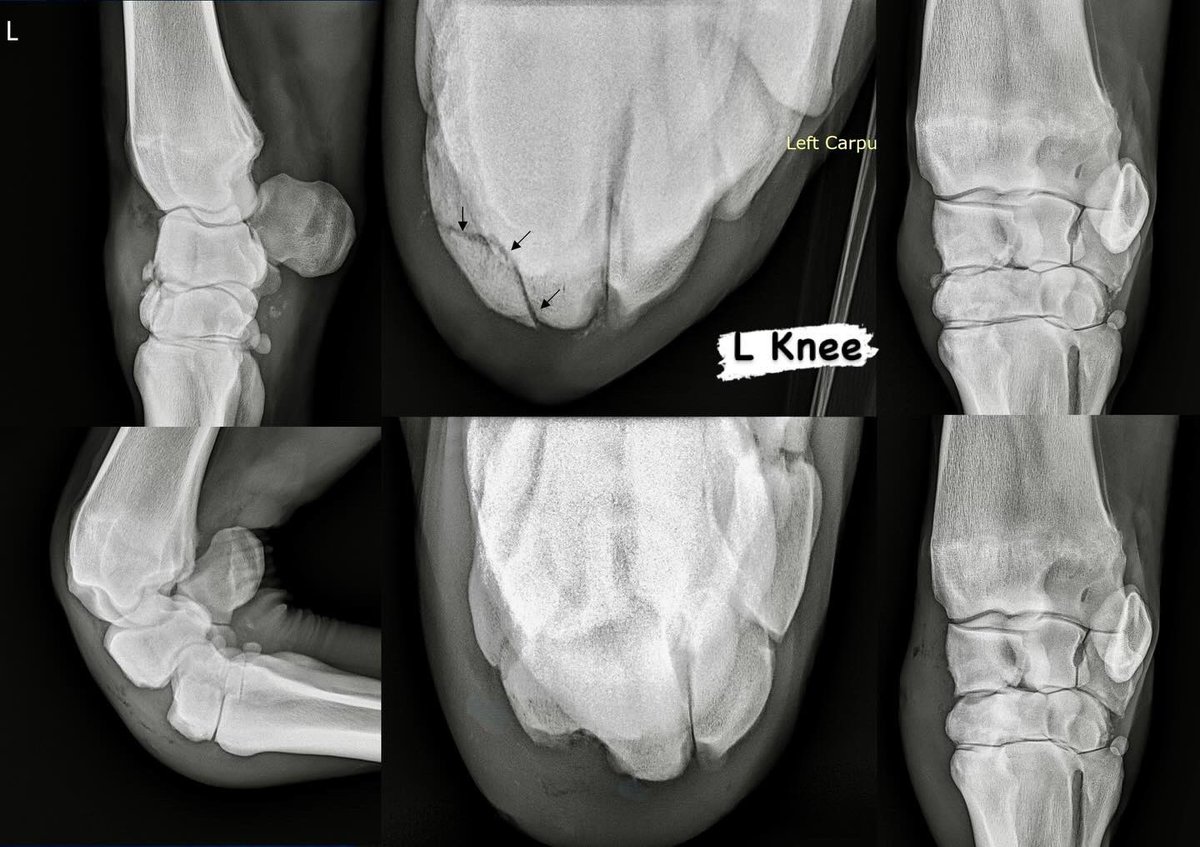

This big beautiful TB filly incurred serious injuries to both of her knees while on the lead in the stretch of a race this weekend- an extremely rare occurrence to experience bilateral slab fractures😱. Fortunately she had immediate expert care from her jockey, the outriders, attending vets, etc and shipped in to us safely. A lot of arthroscopic clean-up and some hardware added to boot and 24-hrs later we have a much happier horse who will go on now and lead a very comfortable life as a broodmare 🔩🔩🔩